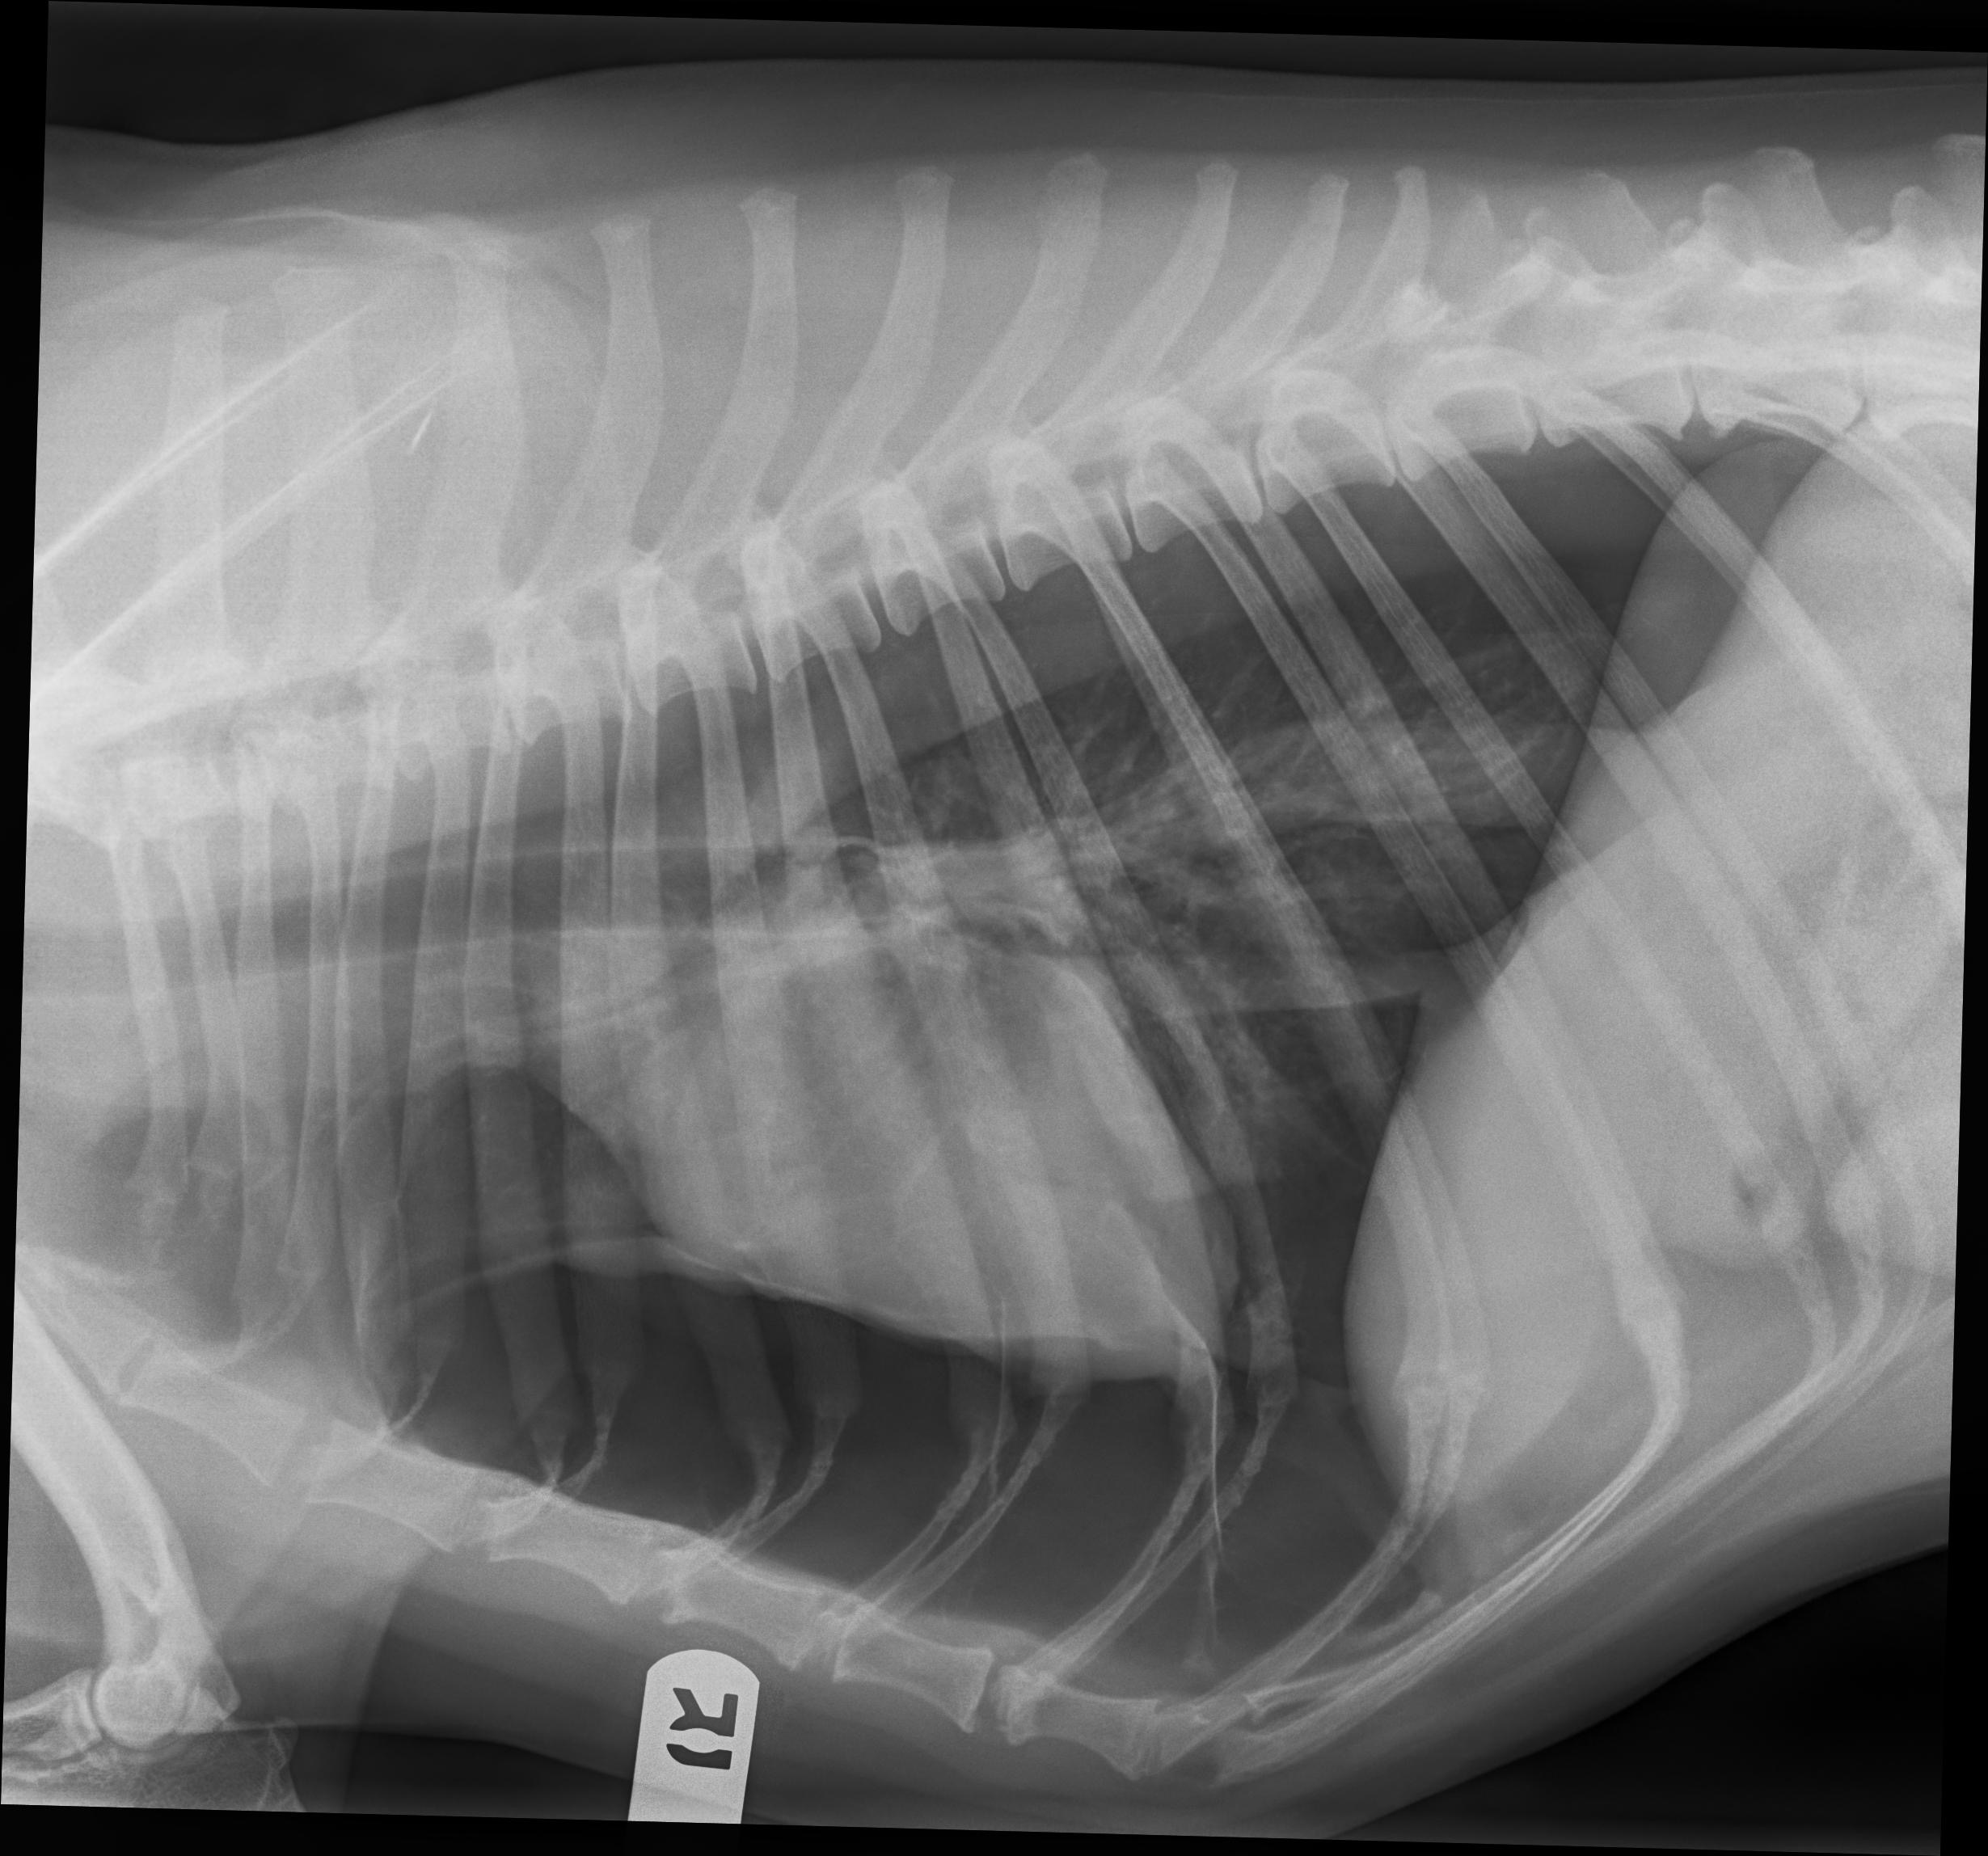

We are currently at BluePearl Emergency Hospital with our beloved Sunshine. What started as a breathing scare has turned into a serious diagnosis: Sunshine has pulmonary bullae (air blisters in the lungs) that are putting her life at risk. She is coming home for now, but may have to keep going back to have her lungs drained until we can hopefully come up with the money for her surgery on Monday. To give Sunshine a real chance to recover, she needs a specialized lung surgery (lobectomy). The cost of emergency stabilization, a CT scan, and this life-saving surgery is more than we can handle alone, and BluePearl requires a significant deposit to begin her treatment.